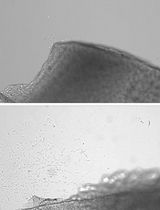

Fetal kidneys with attached bladders are first harvested from donor fetuses. Each fetal kidney–bladder unit is then loaded onto the bevel of a 15–16 G needle. After laparotomy in the pregnant rat, the uterus is exteriorized, and under a stereomicroscope, the needle is inserted transuterinely into the subcutaneous space of the recipient fetus. By expelling the contents of the needle, the donor fetal kidney is transplanted into the subcutaneous compartment of the fetus in utero. MNBs: metanephros–bladder units.